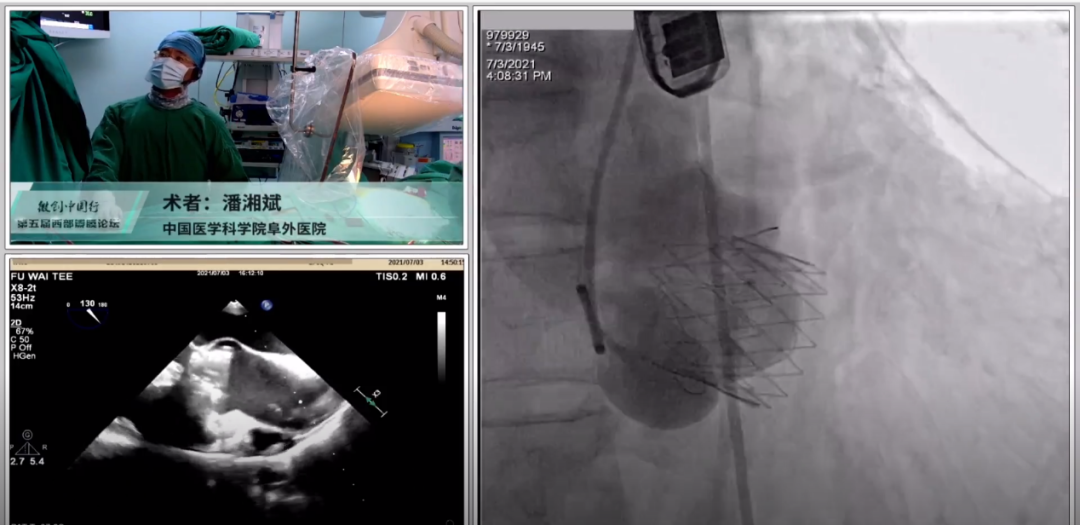

此次大会,四川大学华西医院郭应强教授、中国医学科学院阜外医院潘湘斌教授所带领的团队向与会者精彩呈现了两台J-Valve TAVR手术直播,让与会者更直观地欣赏到两家中心团队高超的TAVR手术技艺,也再一次展现了J-Valve在介入瓣膜领域无可取代的优势。

潘湘斌教授使用J-Valve展示了一台单纯主动脉瓣关闭不全病例。使用27mm J-Valve瓣膜,在影像引导下将定位件精准定位在三个瓣窦内,造影和超声双手段确认下准确释放瓣膜,结果良好,造影显示无瓣周漏。充分展现了阜外医院高水准的TAVR质量控制以及严谨的治学理念。潘湘斌教授表示,J-Valve的独特设计在关闭不全病例上应用良好,是单纯关闭不全病例的最佳选择。中国的心外科医生手术经验更丰富,技术更精巧,相比国外同道,在经心尖手术时处理得更好,并发症概率也比较小,经心尖的术式值得推广。